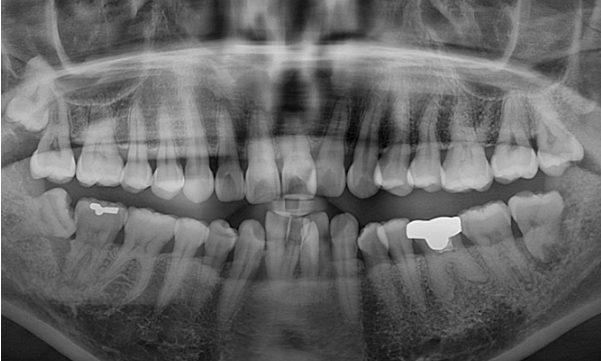

파란 화살표 부위가 치주염이 심한 부위입니다.

앞니 4개 중 3개가 모두 흔들리며 치주염이 깊은 상태여서 발치가 불가피한 상황입니다.

3개 중 2개는 발치를 하고 나머지 1개는 많이 흔들리지만 쓸때까지 쓰다가 나중에 빠지면 보철을 하기로 정하고 교정치료를 했습니다.

교정 후 엑스레이 입니다.

치아 뿌리 축은 양호하고 많이 흔들리던 앞니는 교정용 철사 유지장치를 붙여놨습니다.

관리를 잘 하시면 큰 불편함 없이 쓸 수 있습니다.